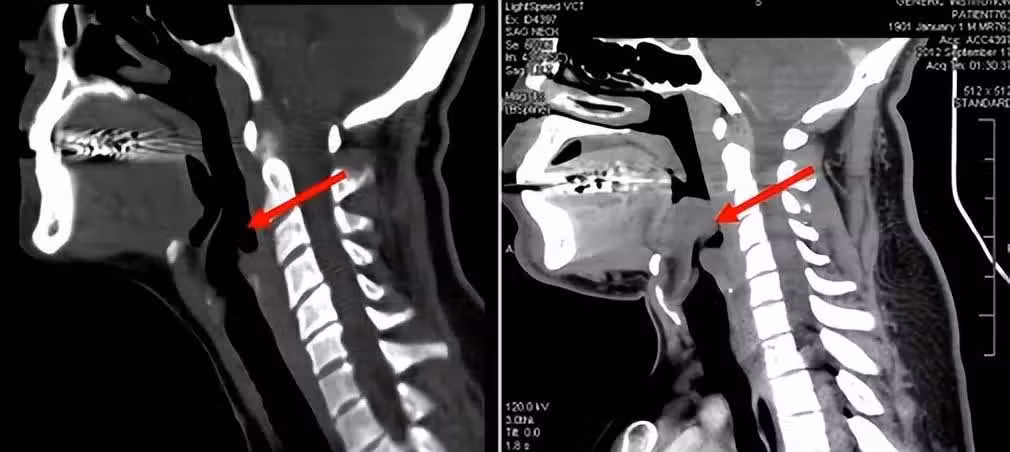

在這些原因當中,最嚴重的要屬變態反應,當抗原(如藥物:阿司匹林;血清,食物:海鮮)等進入機體後,產生某種變應原發生反應,全身性的變態反應會引起會厭區黏膜或杓會厭襞的高度水腫。

除了死亡率高以外,會厭炎還十分容易誤診,這也是這個病兇險的另一個原因。因為發病時,患者一開始的感受基本都是咽痛、吞咽困難,多數人會以為是扁桃體發炎、咽炎或者感冒,一般不會引起重視。